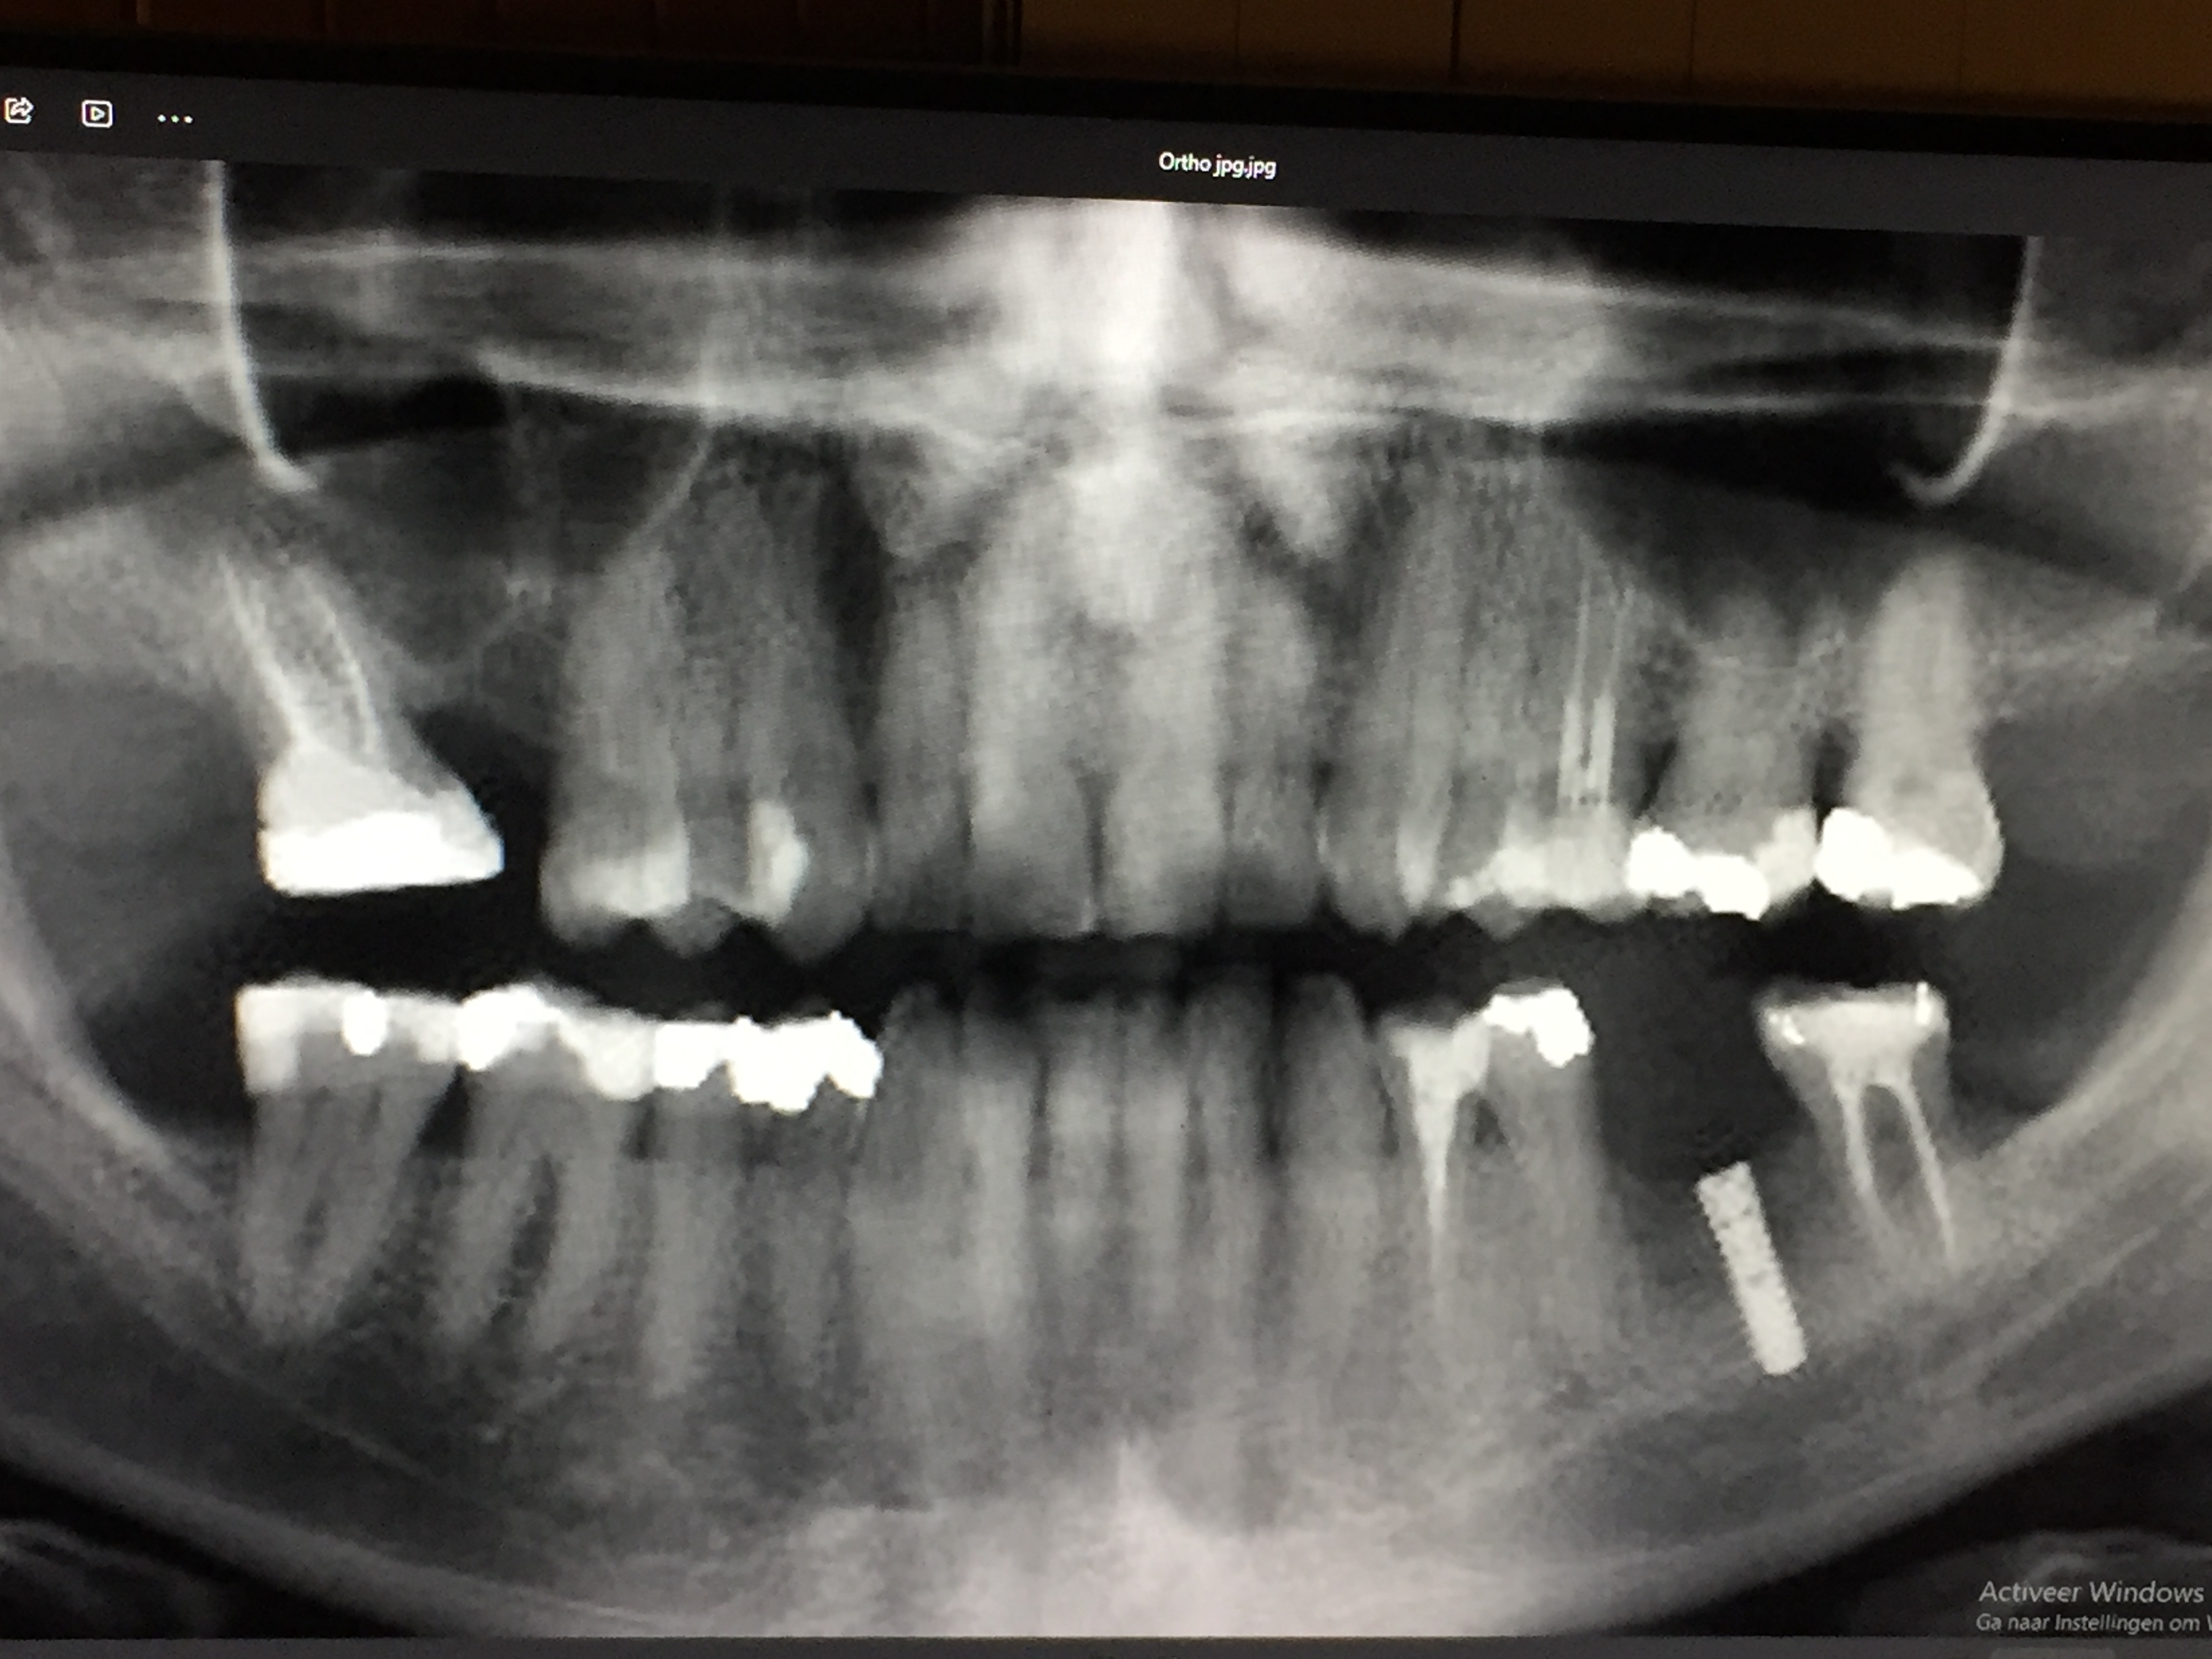

Tandarts_Richa…

Dit is voor mij over duidelijk...sorry. Helaas waarschuwt het lichaam niet altijd gelijk als er iets mis is.

Met nadenken over vervanging bedoel ik ..hoe gaat u de verloren kauwfunctie opvangen...de mogelijkheden afhankelijk v rest gebit. Maak een uitgebreid behandel/stappen plan voor de toekomst v uw gebit/kauwvermogen. Laat een panorama foto maken. Daar staan alle wortelpunten op. Bij twijfel nog extra kleine foto. ( hier posten zonder naam vermelding geef ik mijn mening)

Als ik de laatste foto bekijk dan zijn er een paar zaken die ik mij afvraag.

- Is er een totaal plan gemaakt voor herstel v h gebit. Beginnend bij de ophanging...uw bot verlies.

- Als een wkb gedaan wordt adviseer ik altijd een knobbel overkappend vulling of een kroon waarbij een kroon vaak mijn voorkeur heeft.

- Er zijn vele grote vullingen... zijn daar adviezen voor kronen gegeven.

- Bij de 36 is een advies impl gegeven om de verloren gegane ruimte op te vullen... hoe zit dat rechts boven..welk advies.

- resorptie (intern of extern) is niet altijd te voorkomen dus als daar een kroon was geplaatst was het misschien toch gebeurd,,,of was er een lekkage die in de loop der jaren groter is geworden.

Dit is een waarschijnlijk oude foto dus ben benieuwd hoe het er nu uitziet.

Allemaal vraagtekens. Daarom is een x-foto bibliotheek voor mij belangrijk om het proces v gebeurtenissen te begrijpen en op in te spelen.